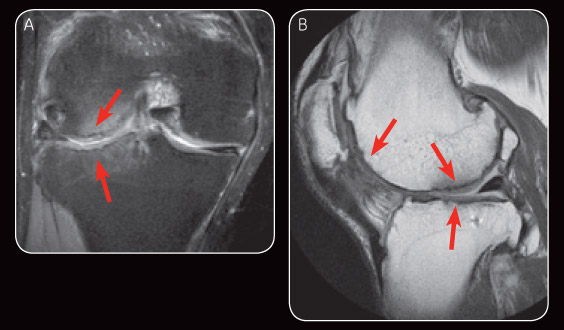

Interval MR exams by 1.5T ONI MSK Extremity MR has shown satisfactory healing of the chondral defects including the subchondral bone. The MR images also clearly showed evidence of cartilage regeneration. This newfound innovative procedure is not limited to small isolated lesions but can be used to treat large, multi-compartment lesions, including “kissing lesions.”

Fig. 3 Appearance on MR image at six-month follow-up demonstrates satisfactory repair cartilage and minimal subchondral oedema (A). Sagital PD at six-month follow-up also demonstrates satisfactory repair cartilage (B).